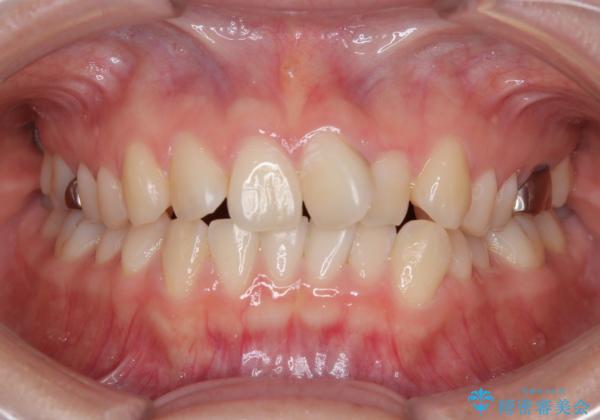

- 「前歯のねじれを改善したい」とのご希望で当院に来院された患者様です。

診察の結果、上下の前歯部に**叢生(そうせい/歯のガタガタ・重なり)**が認められました。

特に上の前歯にはねじれや重なりがあり、審美的にも清掃性にも影響している状態でした。